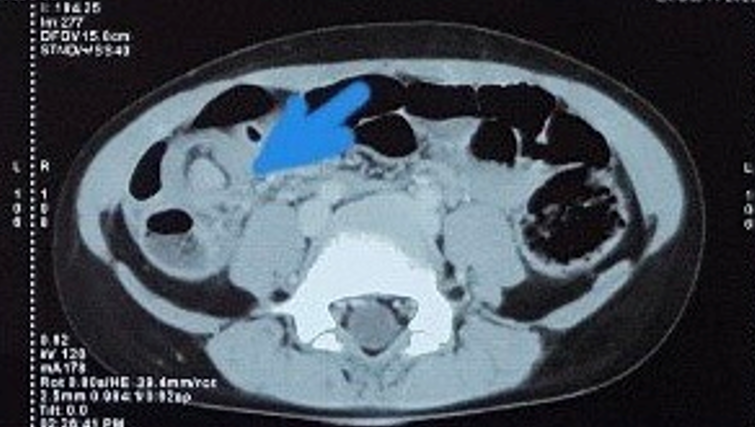

polyp đại tràng… các bác sĩ đã cho bệnh nhân chụp CT ổ bụng có thuốc cản quang

để tìm nguyên nhân gây bệnh. Trên phim chụp CT ổ bụng phát hiện bên cạnh khối lồng

là hình ảnh khối u manh tràng đường kính 3cm.

Hình

1: Phim CT ổ bụng, mũi tên màu xanh chỉ khối lồng và khối u manh tràng